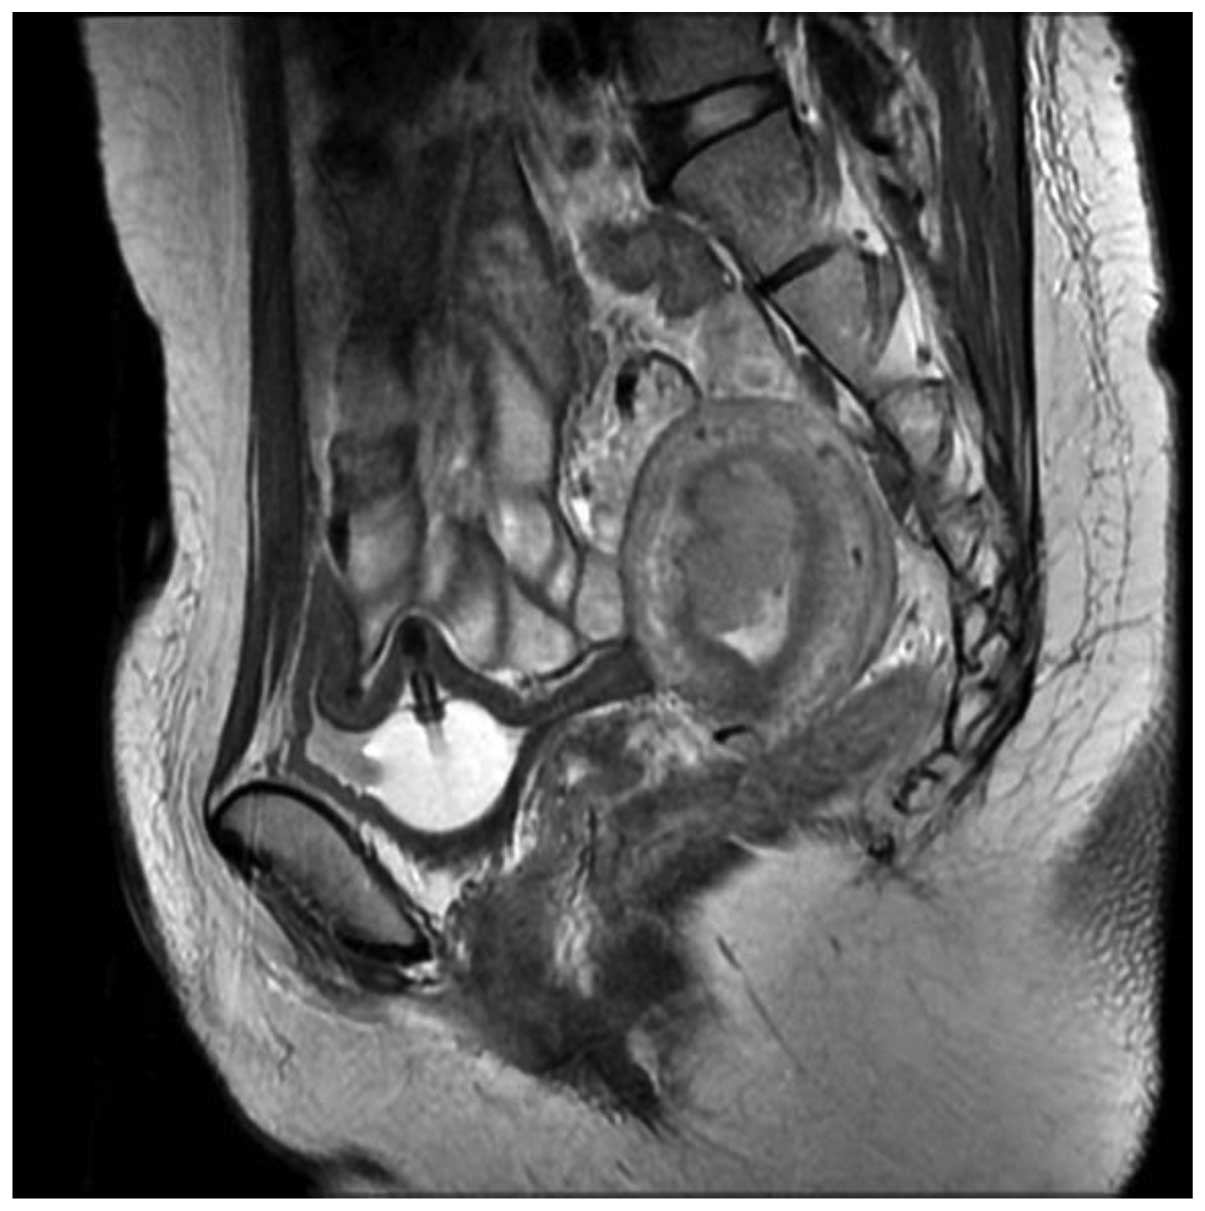

12+ Endometriosis Mri Images Gif. It may attach to the ovaries, fallopian tubes, the exterior of the uterus, the. It manifests in three ways;

Like ultrasound, magnetic resonance imaging (mri) is an. Endometriosis is an abnormal growth of endometrial cells found in the uterus. Endometriosis is a benign disorder characterised by proliferation of endometrial tissues outside the endometrial cavity.

Uterus appears bulky for age and retroverted in position. It manifests in three ways; Sign up for the my medlineplus newsletter what's this? The resulting images might help your doctor identify endometriomas, or chocolate cysts. mri scans are another type of imaging technique that can help diagnose endometriosis.